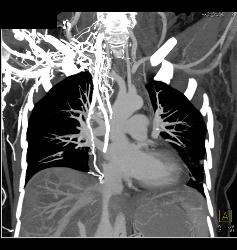

Para-cardiac Nodes in A Carcinoid Patient